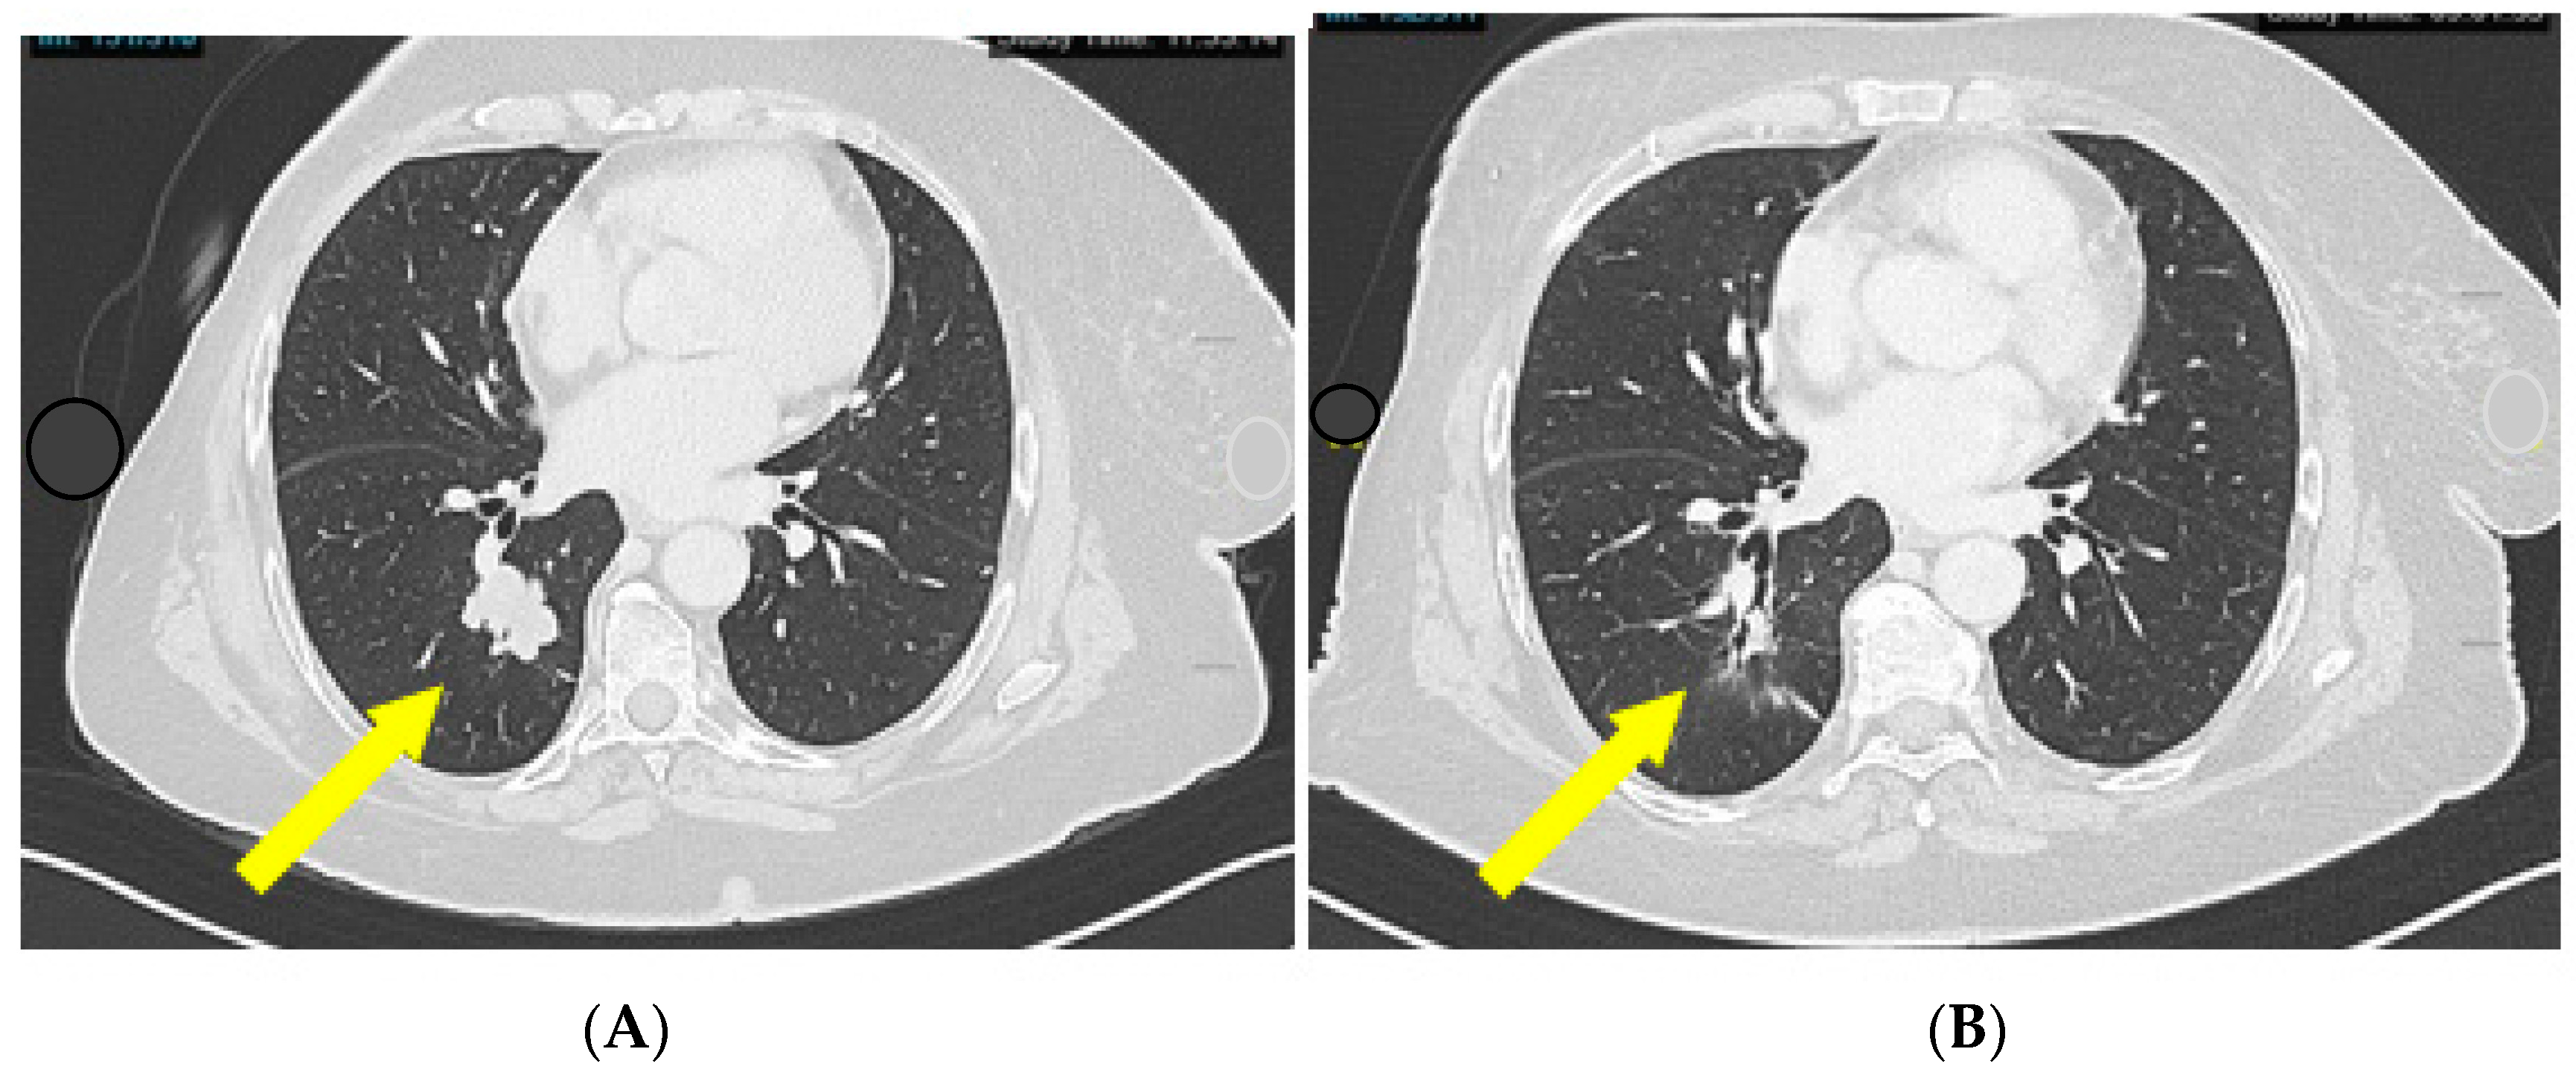

- Case 1: